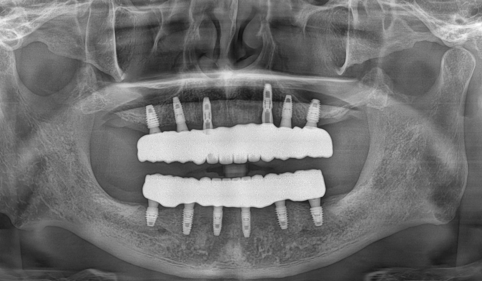

CT 촬영으로 뼈 상태를 꼼꼼히 확인해보니, 사실 굳이 뼈이식이 필요하지 않더군요..

뼈 밀도도 충분했고, 임플란트를 잘 선택만하면 굳이 뼈이식 없이도 안정적으로 심을 수 있었던 거죠.

CT와 3D 디지털 진단을 통해 뼈 상태를 세밀하게 분석한 후, 가능하다면 뼈이식 없이 바로 임플란트를 심는 방식을 우선 고려합니다.